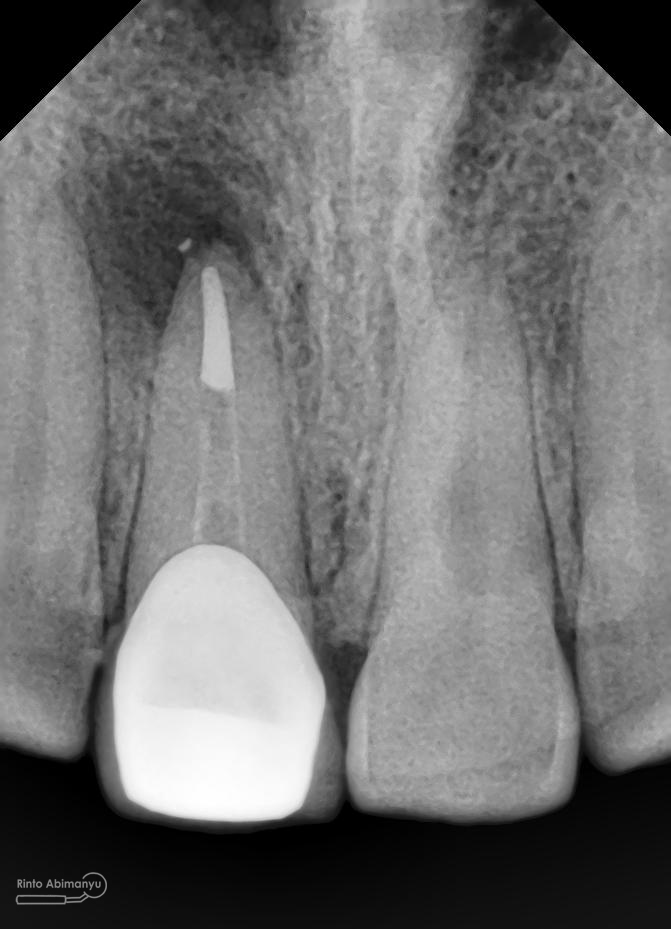

Foto radiografis akhir

Dari foto ronsen terlihat gambaran yang “indah” dari mulai pengisian saluran akar yang rapat dan padat serta gambaran sementasi mahkota yang terlihat homogen….

Oo iya tidak lupa juga dilakukan foto ronsen setelah pemasangan crown…